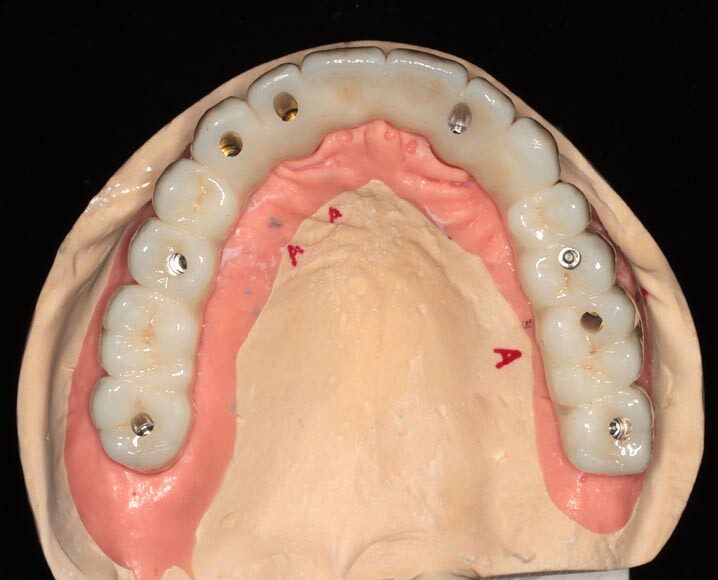

Three months post, first surgery the patient returns for implant uncovering and these are the impression copings preparing for the fixed temporary bridge.